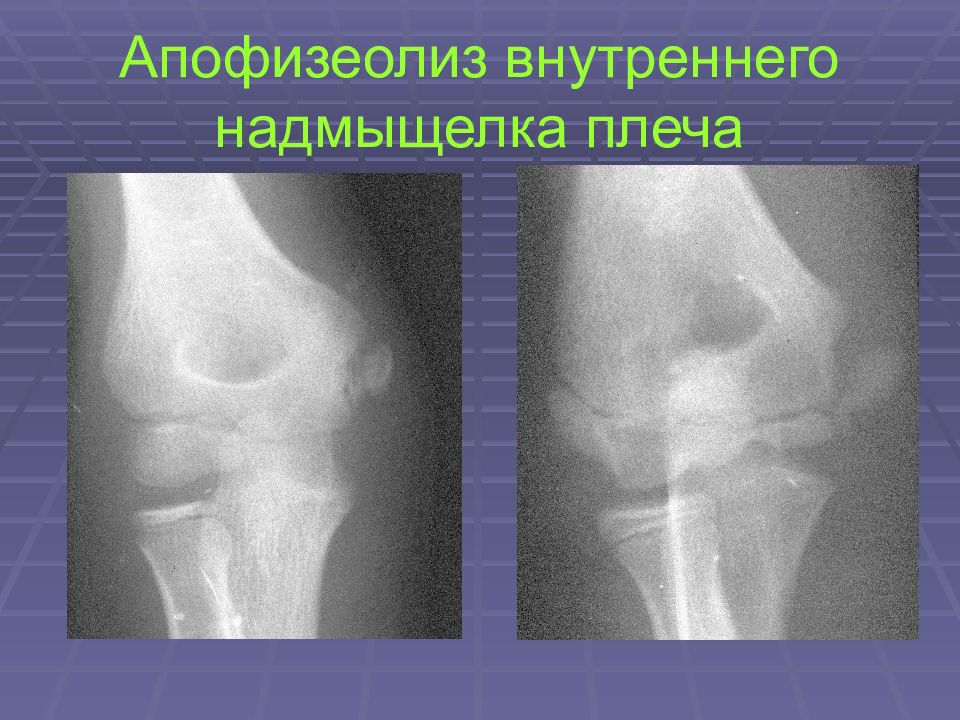

Слайд 26: Апофизеолиз внутреннего надмыщелка плеча

Слайд 27: Апофизеолиз внутреннего надмыщелка плеча

Слайд 28: Апофизеолиз внутреннего надмыщелка плеча

Слайд 29: Апофизеолиз внутреннего надмыщелка плеча